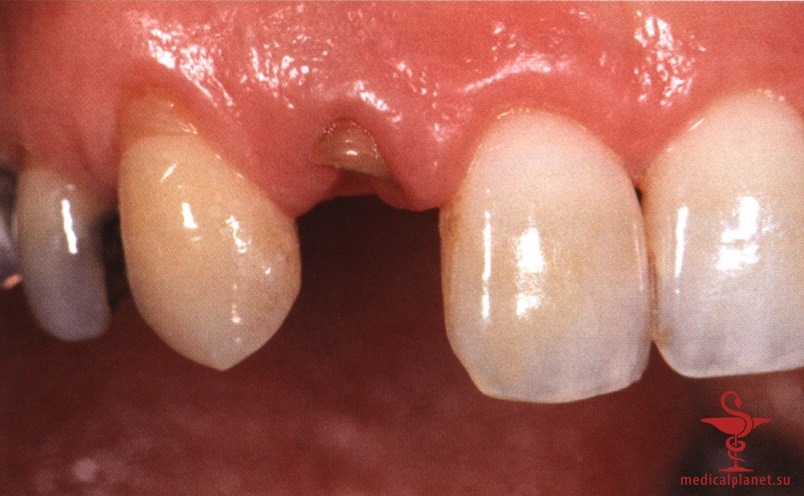

В частности, в эстетически значимой зоне имплантат не следует устанавливать в положении и направлении корня замещаемого зуба, поскольку в большинстве случаев это приведет к слишком вестибулярному положению и избыточному вестибулярному наклону имплантата. Обычно такая ситуация ассоциируется с выраженной рецессией десны, как это описывалось в отдельной статье на сайте (просим Вас пользоваться формой поиска по сайту выше) (рис. 1).